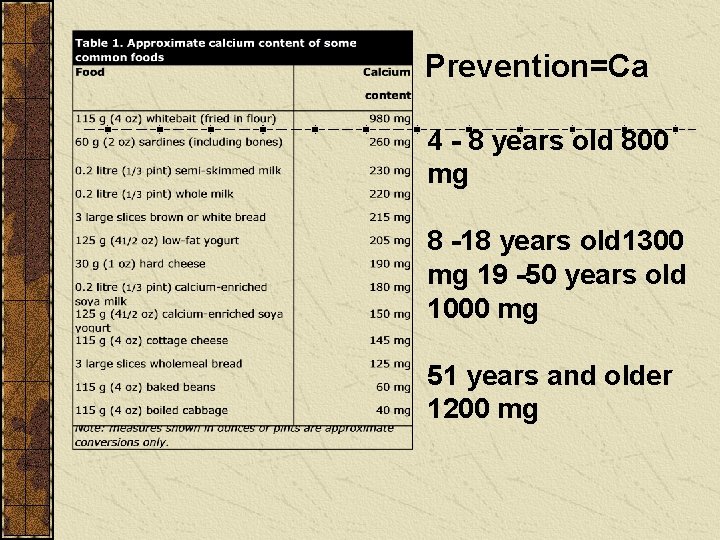

Prevention=Ca 4 - 8 years old 800 mg 8 -18 years old 1300 mg 19 -50 years old 1000 mg 51 years and older 1200 mg

Osteoporosis Detection Bone density test Treatment Calcium and vitamin D Hormone replacement therapy (HRT)